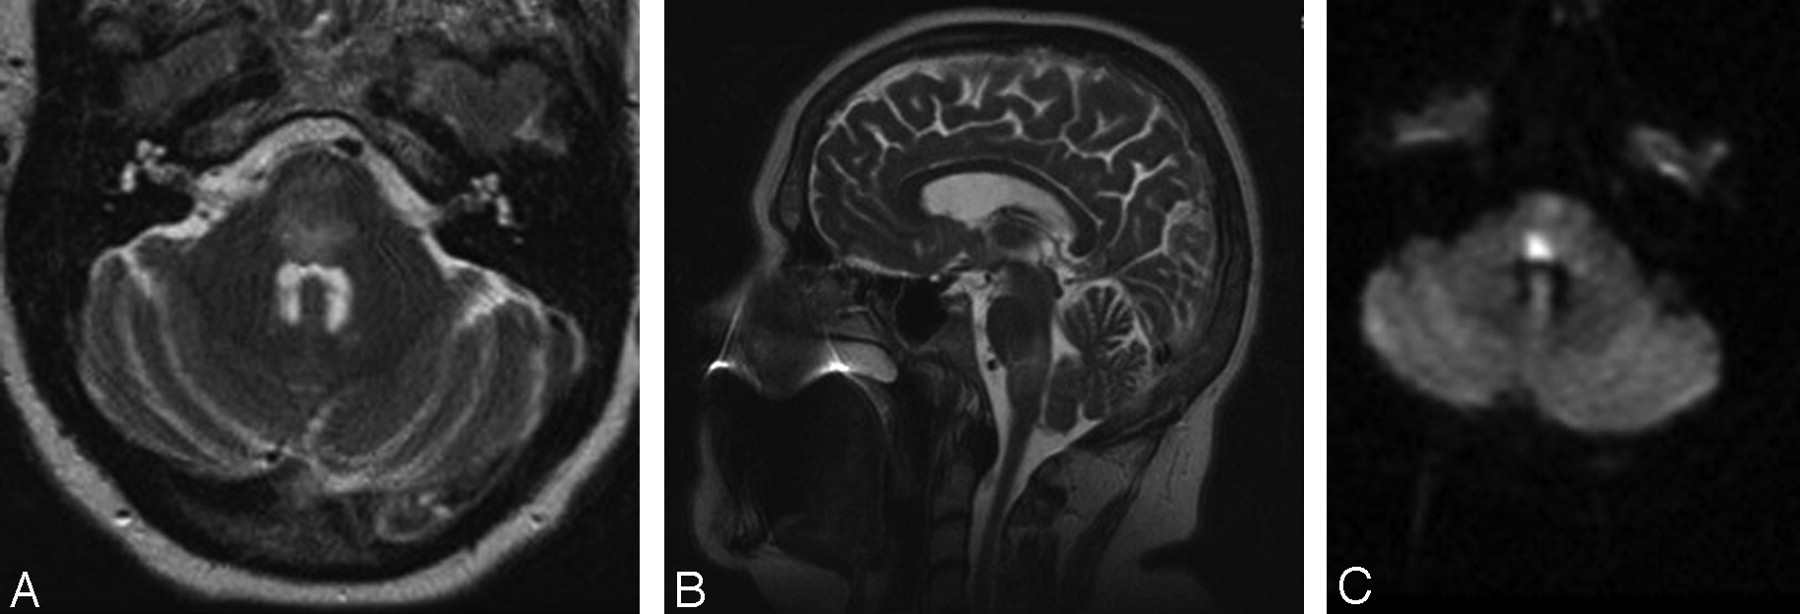

Repeat MR imaging 3 months after IPSS demonstrated very scant T2-weighted abnormality, except in the region coinciding with the fixed DWI abnormality in the dorsal pons (Fig 3). At 6-month follow-up, she reported diminished diplopia but had persistent bilateral lateral gaze palsy. She did, however, have complete resolution of her right facial weakness and left-sided hemiparesis. In addition, her tracheostomy had been reversed and her swallowing was substantially improved.

MR imaging at 3 months after IPSS. Axial T2-weighted MR imaging demonstrating near-complete resolution of edema within the brain stem but a region of hyperintensity within the dorsal pons corresponding to the region of infarction.

In our 5½-year experience, 44 patients underwent IPSS after either an equivocal work-up or after previous failed surgery. The initial 35 consecutive patients sustained no complications as a result of the procedure, and the 8 most recent procedures have also been free of complications. However, 1 of 44 patients did sustain a partially reversible brain stem injury. After reviewing the literature, we believe that the prominent anterior pontomesencephalic veins seen in our patient during the right IPS venogram was an example of a variant pattern of venous drainage surrounding the brain stem and contributed to her injury. Whether this was from the catheter occluding venous outflow or from focal venous hypertension as a result of contrast injection remains unclear. There is some evidence of contrast reflux superiorly into the cranial aspect of the anterior mesencephalic vein instead of only inferior venous drainage (Fig 1B). This raises the possibility of some degree of outflow obstruction or slowing. During the procedure, the patient reported no symptoms, and there were no changes in the patient's examination or vital signs that would have caused us to terminate the test. The resulting injury on the first MR showed diffuse brain stem edema with a smaller region of actual infarction. The region of injury seen on T2-weighted sequences is consistent with our patient's neurologic examination with involvement of the fibers of pontomedullary cranial nerves (VI, VII, IX, and X), the paramedian pontine reticular formation, medial longitudinal fasciculus, portions of the corticospinal tract, medial lemniscus, and spinothalamic tracts. As the edema in the brain stem resolved, best seen on the evolution of T2-weighted sequences on serial MR imaging, the patient's sensory, motor, and lower cranial nerve deficits also resolved. The resulting infarct on the 3-month follow-up MR imaging confirmed a persistent abnormality on T2-weighted sequences within the dorsal pons that extends ventrally (Fig 3). The patient's neurologic examination after 6 months suggests that with the resolution of brain stem edema, only the fibers of the sixth cranial nerve, medial longitudinal fasciculus, and paramedian pontine reticular formation remain damaged. On the basis of the MR imaging findings, this is not surprising.